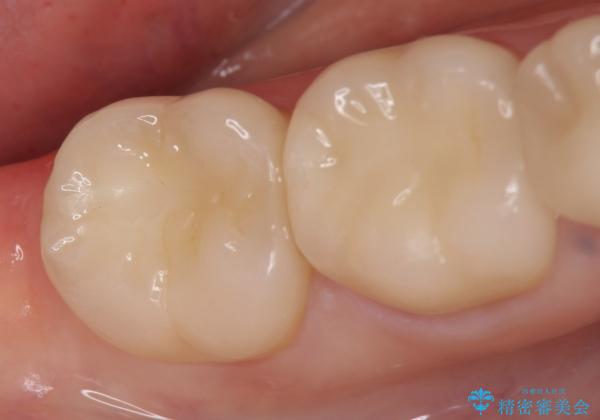

右下6は神経が死んでいたため根管治療を行い、オールセラミッククラウンによる補綴を行いました。

右下7は冷たいものがしみていたため、銀歯を除去後、オールセラミッククラウンによる補綴を行いました。

今回用いたオールセラミッククラウンはジルコニアフレームという白い素材の上にセラミックを盛っているため、審美性が非常に高いのが特徴です。

また、ジルコニアは人工ダイヤモンドの材料にも使われているほど高い強度を持っており、そのためオールセラミッククラウンは審美性だけでなく、奥歯やブリッジの補綴も可能とするクラウンです。